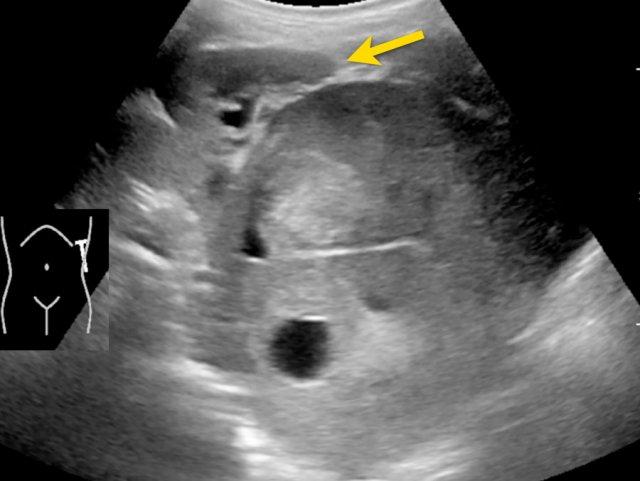

Siêu âm của một bé trai mười lăm tháng tuổi, ban đầu được nghi ngờ có khối u ở thận trái.

Siêu âm cho thấy một khối u nằm kề cực trên phía trong của thận trái. Khối u có vẻ tách biệt với thận. Khối u rất không đồng nhất và có nhiều vôi hóa.

Những phát hiện này phù hợp với u nguyên bào thần kinh hơn là u nguyên bào thận.